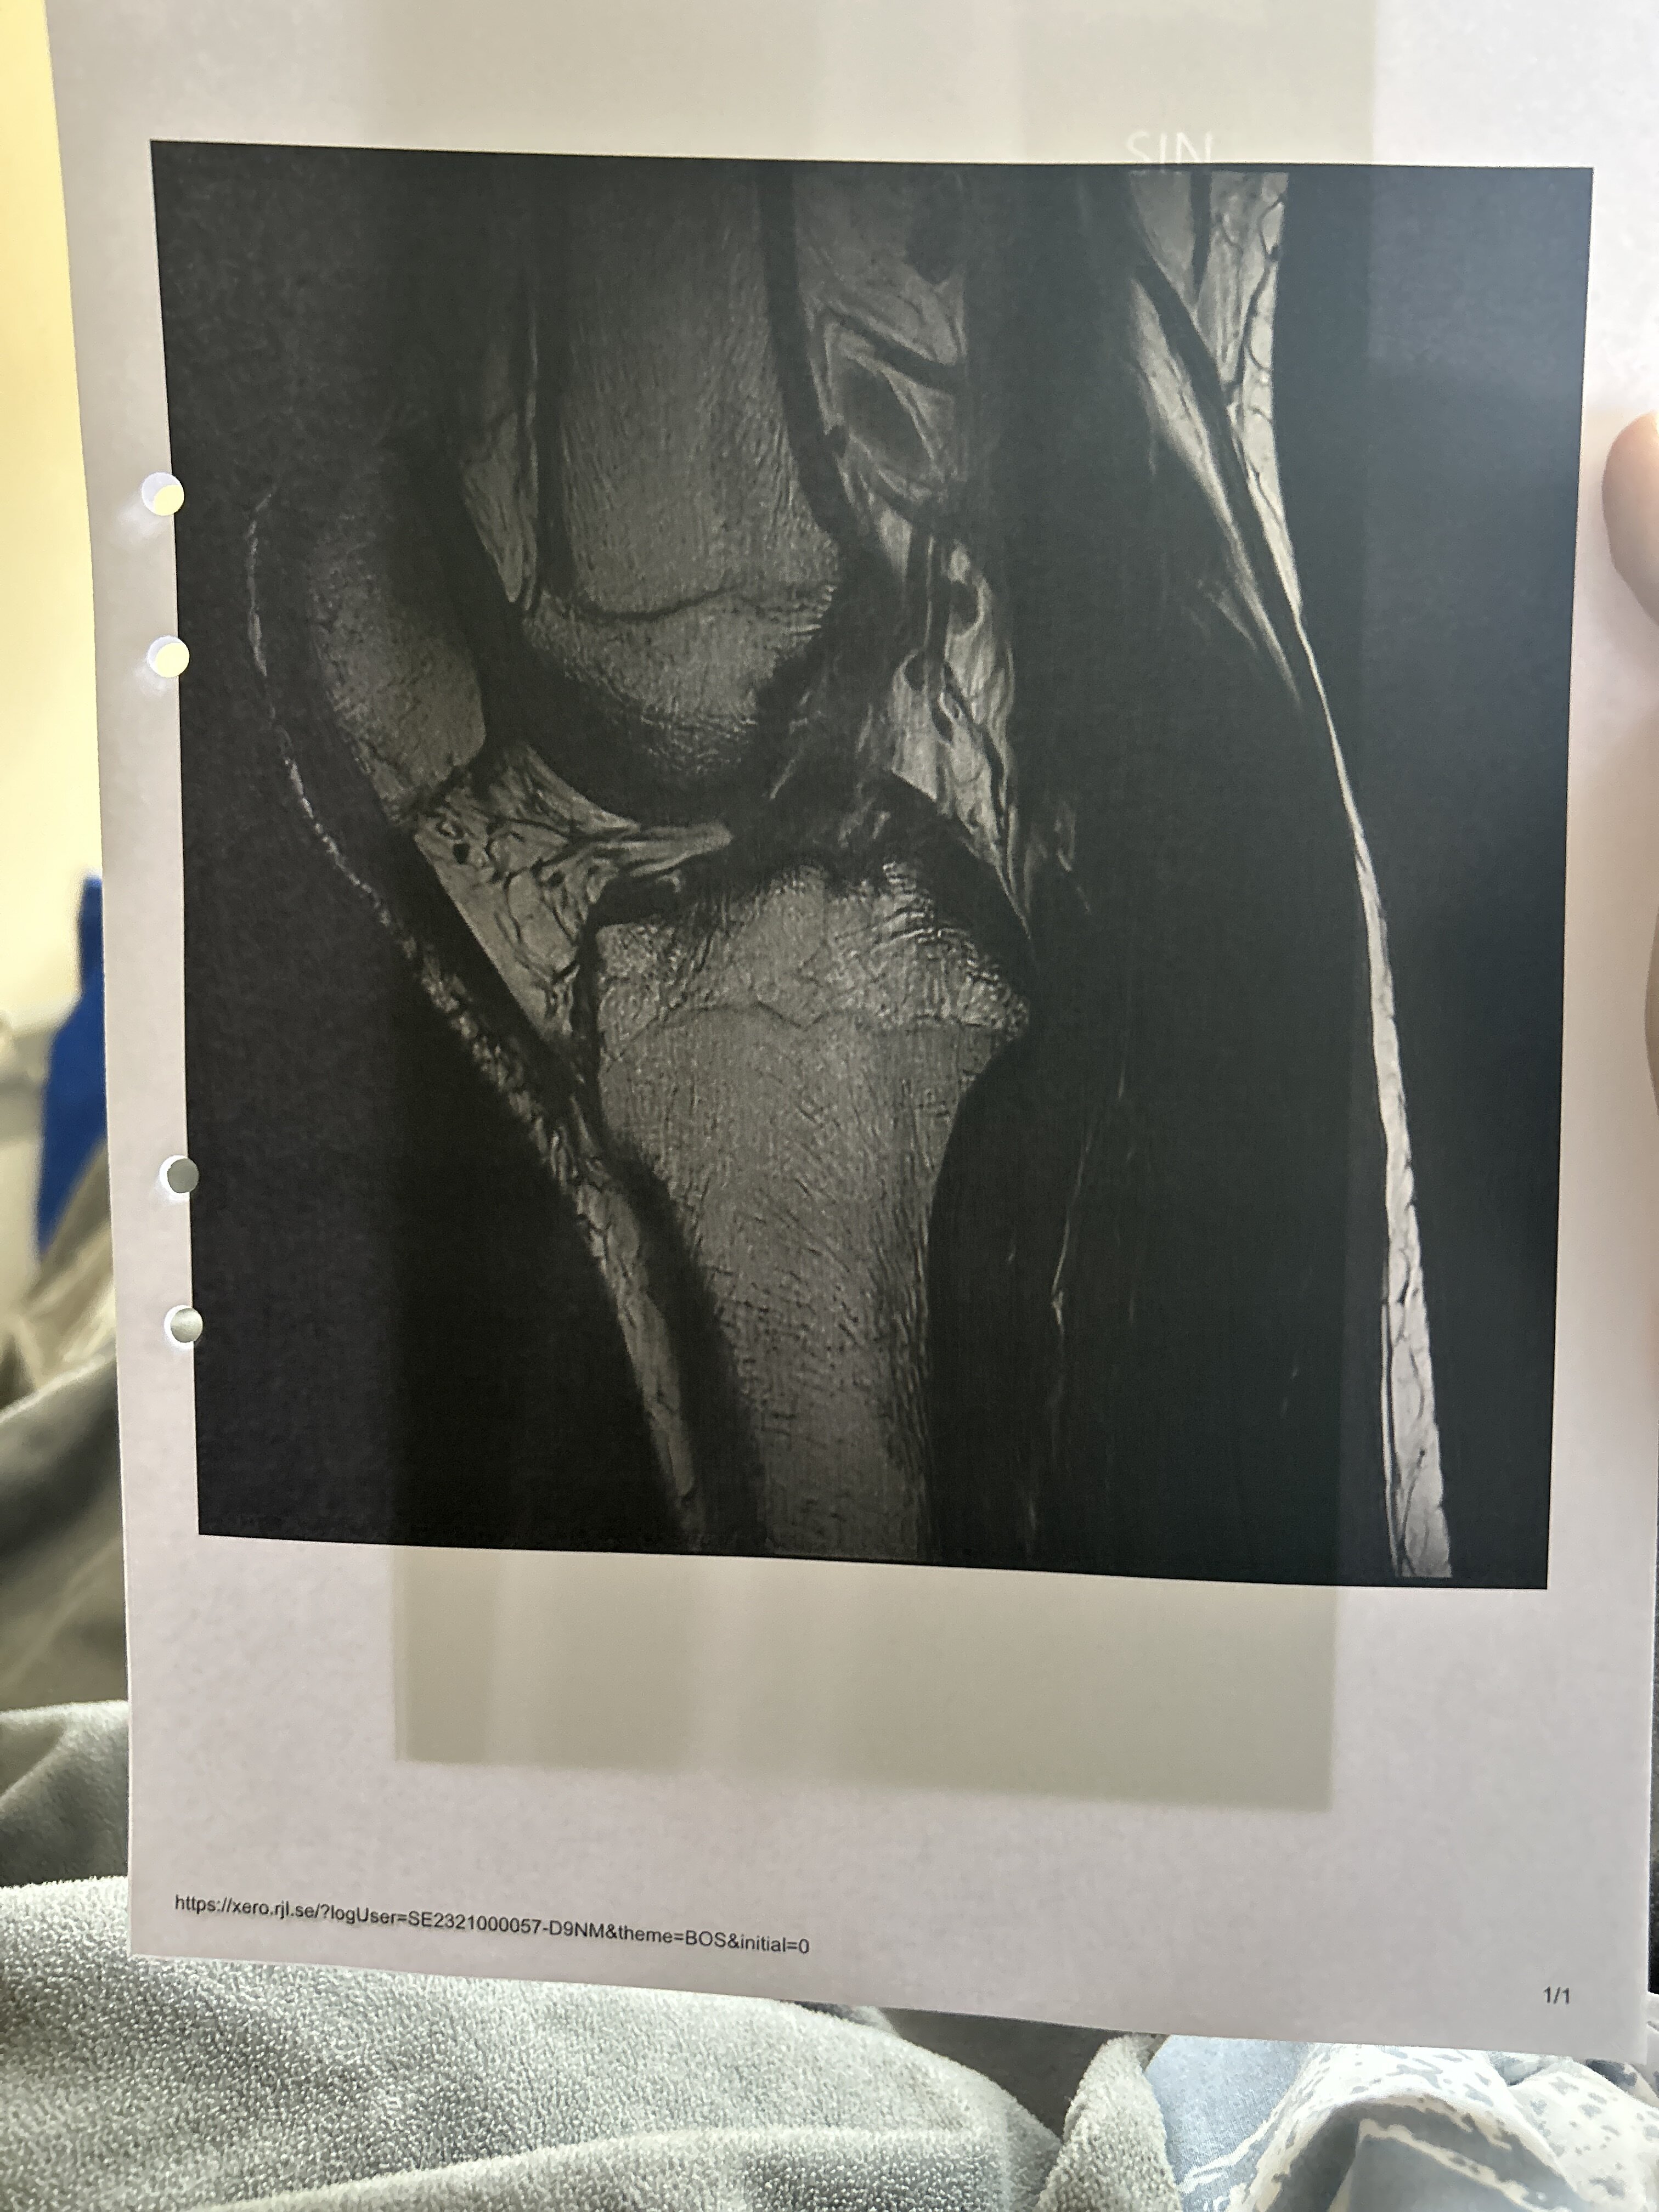

So yea they cut the bone right under my knee and angled it so that it would be straight, then screwed metal plates on it. The plate is on the INSIDE of my knee btw, so yea pretty cool, btw for anyone wondering you dont really gain that much in height, i havent seen myself if im taller because my leg is COMPLETELY numb but ill tell yall if i even get taller, this was more to fix the biggest failo in my body appearance. The photo doesnt show it enough but my legs are the first thing you notice when im in shorts for example. Ill be posting a video later talking about the surger because some pretty fun stuff happened hahahah. Oh i just remembered heres an MRI scan of my knee BEFORE:

Its a big close up but you can see its REALLY fkn curvy